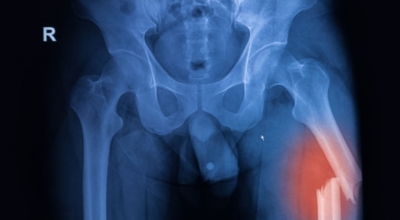

글루코사민에 대조해 원료가 100배가량 비싼 고가의 원료인것으로 알려져 있답니다. 관절염 이유가 되는 것으로는 관절 연골이 닳아 없어지기 때문인데 퇴행성 질환이라고 하는 이유가 연골이 더 이상 생성되기 어렵기 때문이죠. 특히 콘드로이친이라 하는 성분이 나이가 들면서 길이가 짧아지고, 크기가 줄어들기 때문에 연골 구조가 변화되어 가면서 무릎뼈의 간격이 좁아져 통증을 유발하는 원인이 되는데 이 경우에 콘드로이친 효능을 바라볼 수 있답니다.

콘드로이친에는 관절 통증 감소 효험도 있어요. 콘드로이친은 보통 관절염으로 인한 무릎 통증을 관리하기 위해 사람들이 다량 필요로 하는 물질입니다. 관절염의 증상을 덜어줄 수는 있지만 섭취로 인한 효과가 영구적으로 지속되지는 않습니다. 그렇기 때문에 별개의 관절염 치료와 복용을 병행하시는 것이 더 좋습니다.

콘드로이친 효능 중 가장 대표적인 것이 연골세포를 보존하는 역할이라고 합니다. 콘드로이친에는 연골세포의 분해를 억제시켜 연골세포를 보호해주며 유지시켜주는 기능이 있습니다. 연골은 노화가 진행될수록, 나이가 들 수록 점점 그 크기가 떨어지거나 끊어질 수 있지만 이 때에 콘드로이친이 그 스펀지와 같은 역할을 하여 연골 속 수분을 잡아주어 부드럽고 유연하게 유지할 수 있게 도와준다고 알려져 있답니다.

하지만 콘드로이친은 육체 내에서 자연적으로 생성을 할 수 없어 외부에서 추가적으로 보충되어줘야 하는데 나이가 들면서 점점 콘드로이친이 부족하게 되면 무릎이나 손목의 통증, 관절염 등 자연 노화로 인해 피할 수 없이 오는 질환들이 생길 수 있다고 하네요. 그뿐 아니라 아침에 일어났을 때 주로 일어나는 관절 경직 증상 완화에도 큰 도움을 줍니다.

나이가 점점 들수록 보행 속도가 자연적으로 느려지게 되는데, 그 이유는 바로 관절의 노화 때문이죠. 노화가 진행되면 연골 손실이나 관절 간격이 짧아짐에 따라 관절염이 발생하고, 그로 인해 통증이 생겨 보행력이 점점 저하가 될 수 밖에 없다고 합니다. 그래서 나이가 들수록 콘드로이친을 보충시켜 주는 것이 보행능력 개선에 도움을 줄 수 있는 방법중 하나 입니다.

콘드로이친은 대게 골관절염 증상 관리를 위한 치료제로 쓰이고 있답니다. 미국에서 시행된 골관절염 환자 604명을 대상으로 한 연구에서 콘드로이틴의 골관절염 통증 관리의 효과를 관찰했는데 그 결과, 콘드로이틴이 무릎 골관절염 통증이 있는 사람들의 약 10%가 통증완화와 개선효과를 체험했습니다.

그 이유는, 노화가 진행되는 중장년층에게서 콘드로이친 수치가 저하되는걸 볼 수 있습니다. 이는 곧 연골의 뼈와 뼈 사이 완충효과 및 보호기능 약화로 이어지는데 이를 보충하면 관절염을 해결하는데 도움을 줍니다. 그리고 콘드로이친은 관절세포를 재생시키는데 도움이 되고 외부 충격을 흡수, 완화하는데에도 최고의 효과가 있어요.